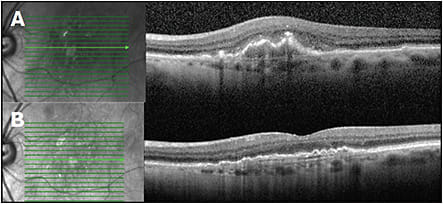

OCT, however, also has the ability to clearly provide information on lesion type. Type 1, Type 2, and Type 3 lesions on OCT correspond to occult, classic, and RAP lesions, respectively.3 Additionally, OCT provides anatomic details of where the fluid is and whether there may be hemorrhage or fibrin on exam corresponding to subretinal hyperreflective material. (Figure 3).

Clinical fundus exam demonstrated intermediate drusen of both eyes with pigment changes in the left eye and no hemorrhage. Figures 4A, 4B highlight the foveal cross-sectional OCTs of the right and left eye, respectively. The right eye demonstrates small drusenoid PEDs. This is notably overlying a thickened choroid with enlarged or pachyvessels. The left eye demonstrates SRF in excess to what would be expected for exudative AMD. There is also a confluent row of PEDS forming a double-layer sign.